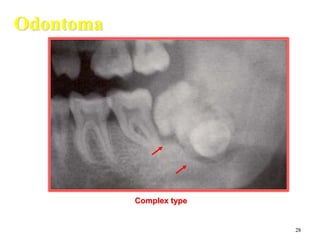

Odontoma

Complex type

Odontomas are developmental malformation

( hamartoma) of dental tissue, it is not neoplasm

Complex = abnormal mass of Calcification

Complex odontomas

The compound type shows apparent tooth shapes while the complex type

appears as uniform opaque mass with no apparent tooth shapes present